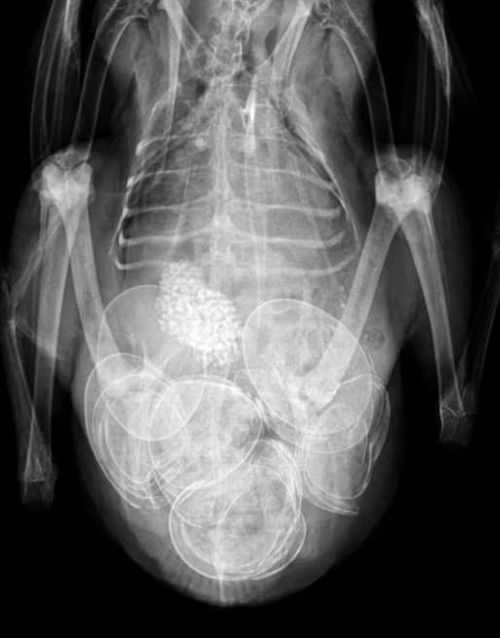

Egg Bound Bird X Ray . The smaller passerine birds tend to. Click here to learn how we treat an egg bound bird. A particularly large egg is often the cause of a bird becoming egg bound. The red circle is showing the proventriculus in this bird. This is the tube just prior to the stomach (gizzard or ventriculus). Eggs shells have a high level of calcium, so depending on how well they are developed, might show up vividly.